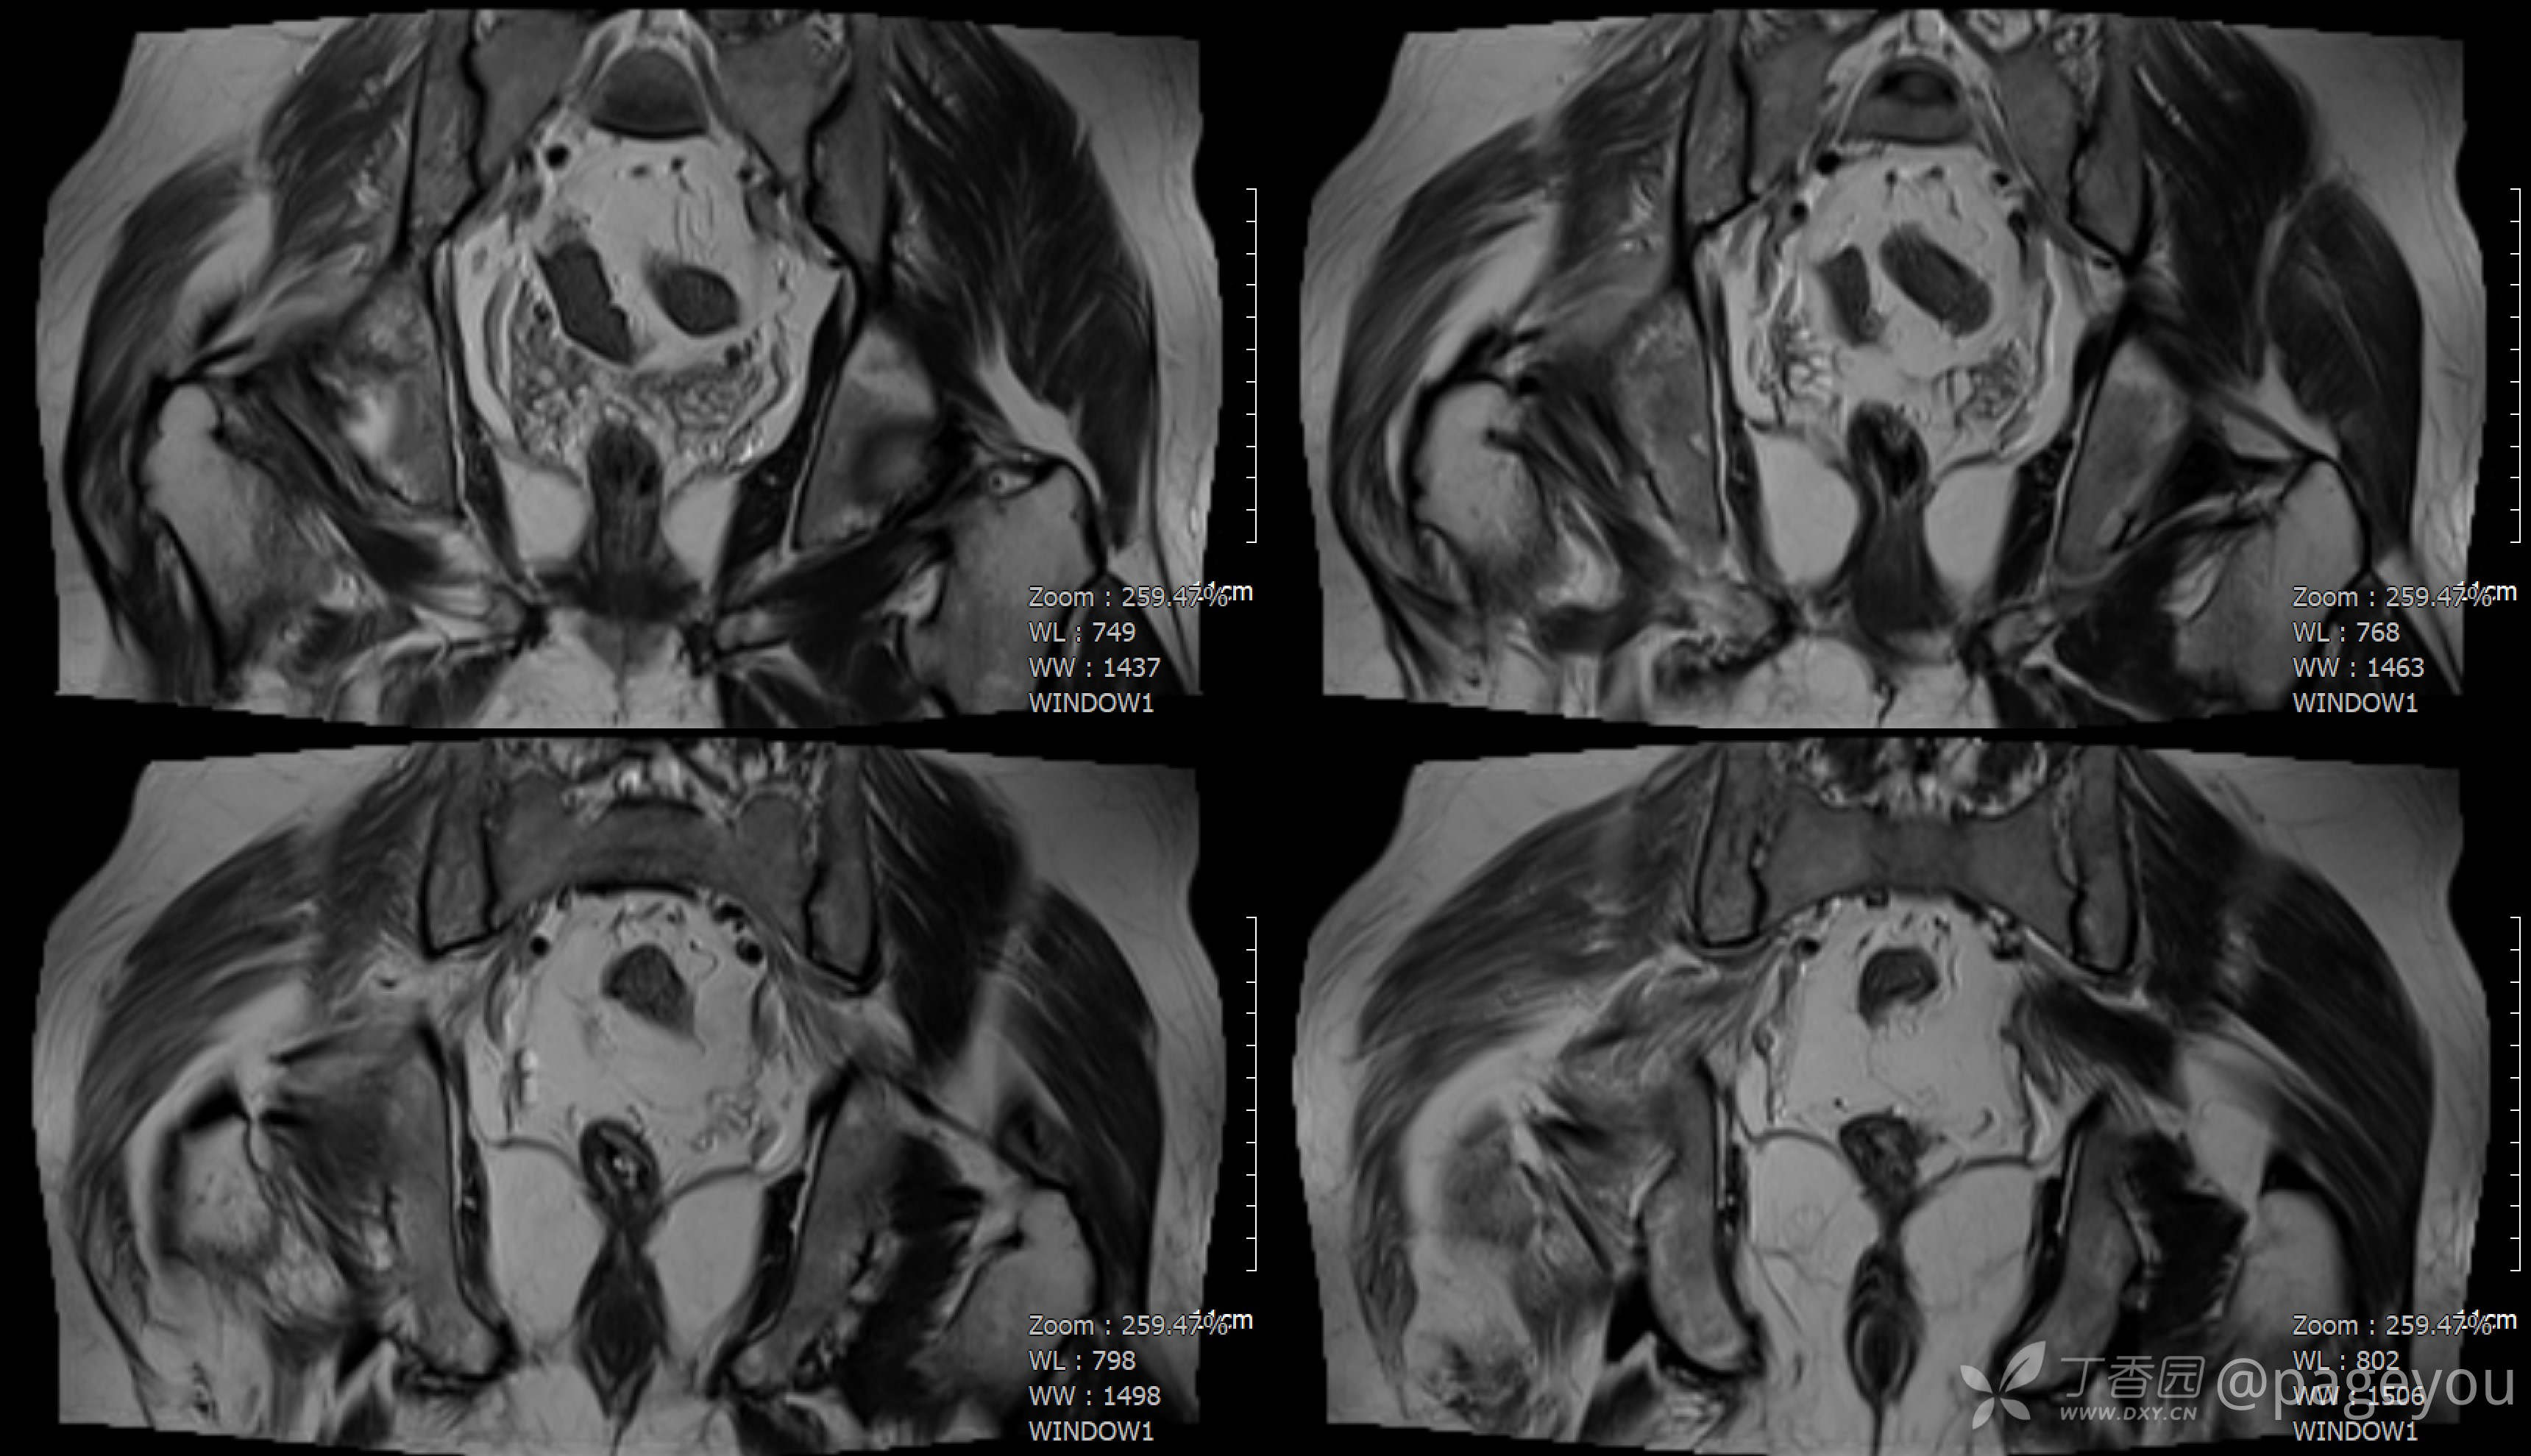

查骨盆MRI: